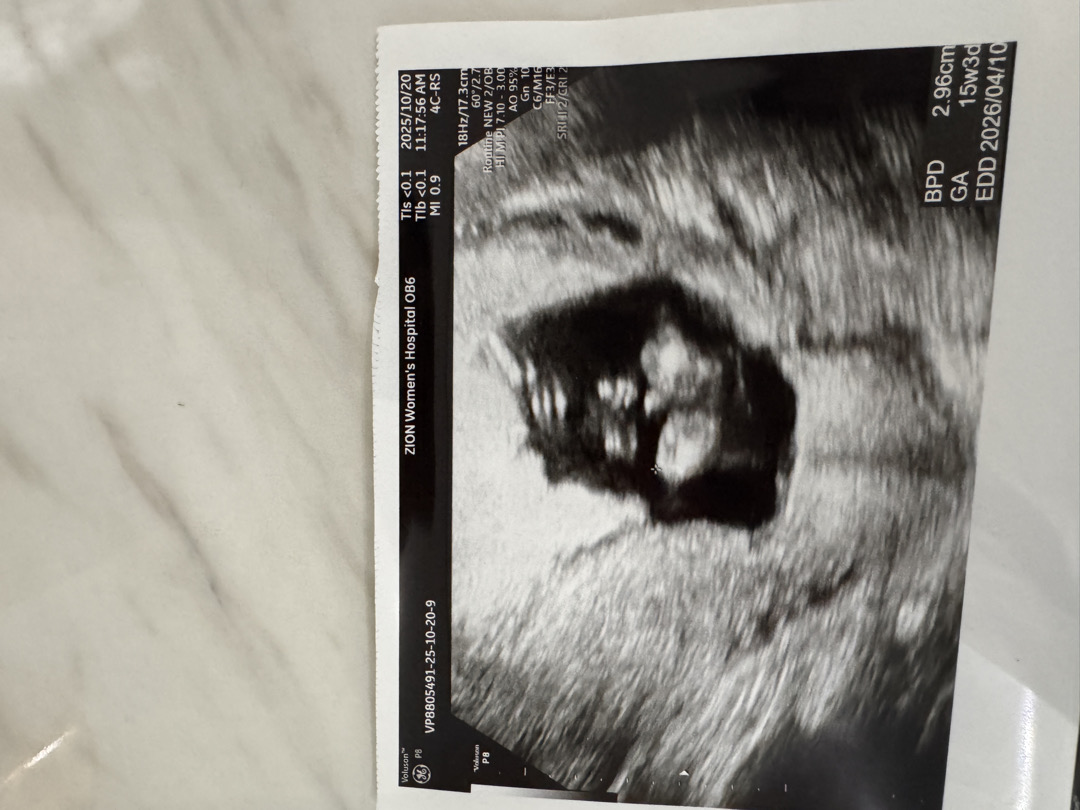

다리 사이 고추인가요 아닌가요!!

15주차인데 의사쌤이 애매하다는데 고추 아닌가요....???? 이게 고추가 아니면 뭐지 뭘로 보이나요 !!

다리가 어디인지모르겠어요 ㅠㅠ